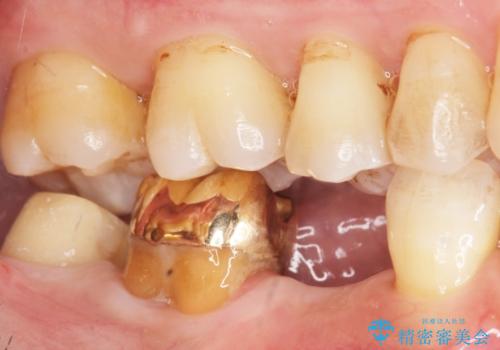

- 右下の奥歯がしみることを主訴に来院された患者様です。

精査したところ、横向きに生えた親知らずのせいで隣の歯(右下7)が虫歯になっていました。

親知らずを抜歯して隣の歯のう蝕を除去し、歯肉の治癒をしっかり待ったのち、患者様のご希望によりゴールド(PGA)クラウンによる補綴を行いました。